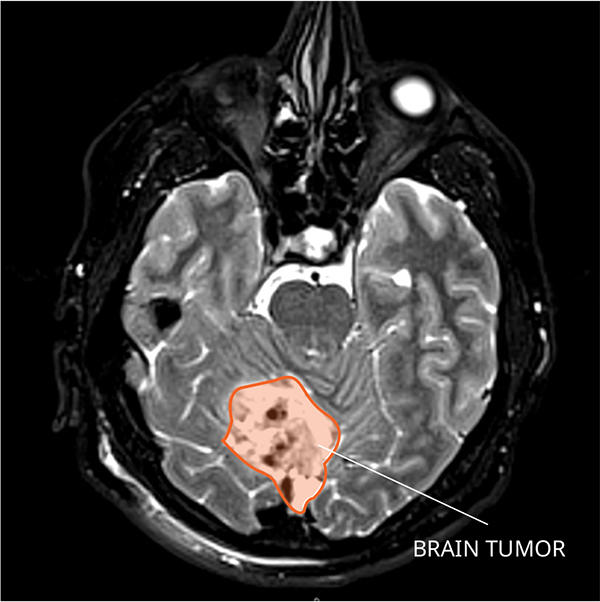

They saw similar results in medulloblastoma, a cancer that forms at the base of the brain near the top of the spinal cord.